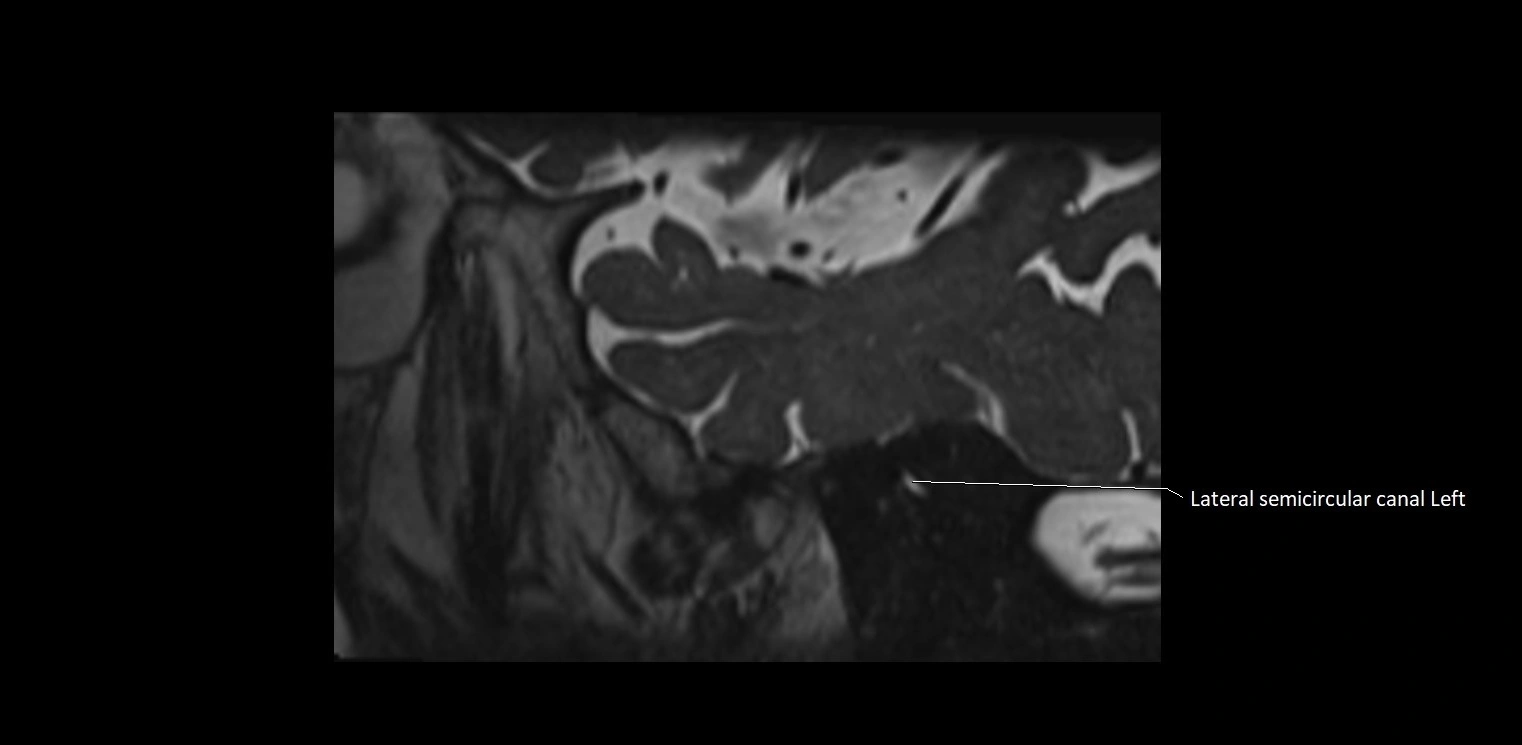

MRI images

image